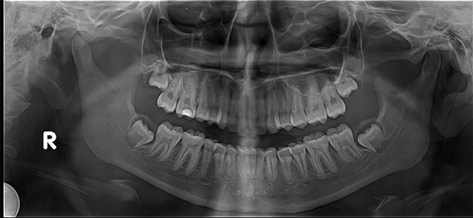

• Panoramic X-rays show the entire mouth area -- all the teeth in both the upper and lower jaws -- on a single X-ray. This type of X-ray is useful for detecting the position of fully emerged as well as emerging teeth, can identify impacted teeth and aid in the diagnosis of tumors.